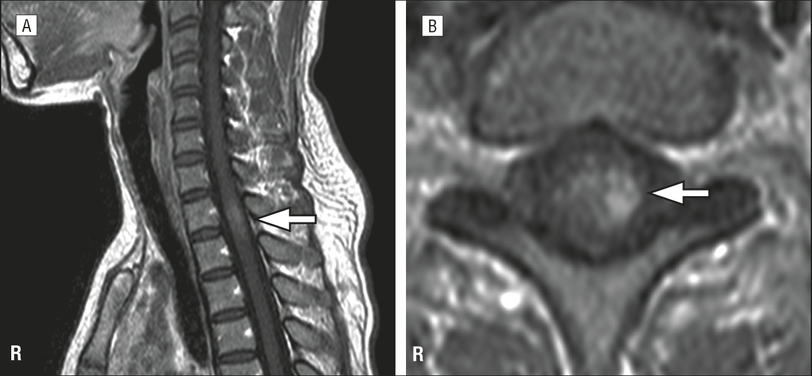

The owl-eyes sign, also referred to as snake-eyes sign represents bilaterally symmetric circular to ovoid foci of high T2-weighted signals in the anterior horn cells of the spinal cord and is seen on axial MR imaging. The sagittal corollary is a "pencil-like" vertical linear high T2-weighted signal extending usually over a number of segments. Although typically described as one of the patterns in spinal cord infarction affecting the anterior spinal artery 1,2, it is seen in multiple other clinical settings and represents the result of increased metabolic activity (thus vulnerability) and reduced collateral supply of the anterior horns of the spinal cord.